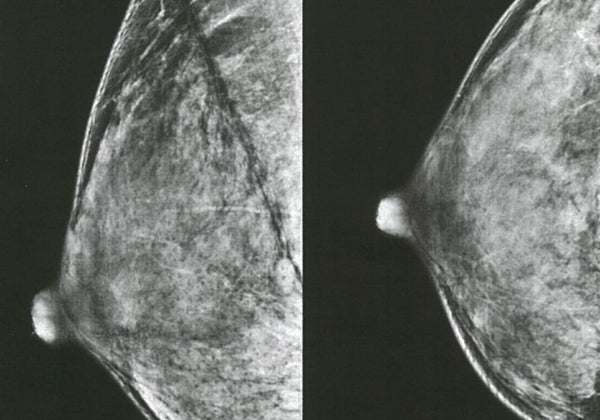

La inteligencia artificial, tan eficaz como dos radiólogos buscando tumores de mama al mismo tiempo

Nuria Ramírez de CastroUn ensayo clínico con 80.000 mujeres demuestra que la herramienta es eficaz y reduce a la mitad la carga de trabajo de los médicos en los cribados de mamografía